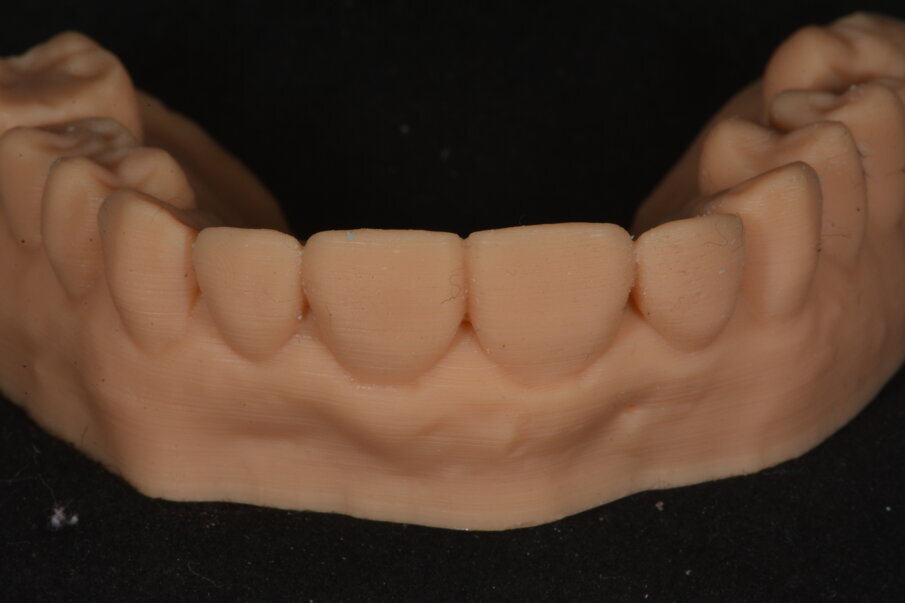

Een digitale afdruk werd genomen waar een digitale tandopstelling op werd ontworpen.

Aan de hand van het digitale model werd een palatale putty gemaakt, die dienst deed als basis van onze nieuwe opbouw.